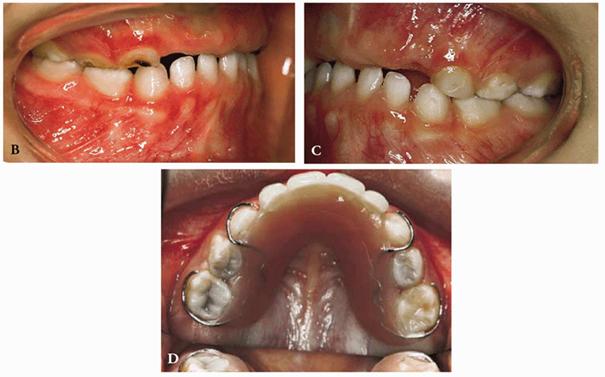

A male patient, 3 years, 9 months old.

PROBLEM: The patient presented with rampant caries, loss of the anterior

teeth, and advanced caries in the posterior teeth (Figure 27-4A

Figure 27-4A: A patient of 3 years, 9 months, with rampant caries and loss of an anterior tooth.

TREATMENT: The root of G is extracted, and the posterior teeth are

restored with composite resins. An attempt to maintain pulp vitality is made by

placing calcium hydroxide on the pulp. A pedodontic prosthesis has been used to

maintain the anterior space, preserve the vertical dimension, improve alveolar

growth, and avoid supereruption of the lower anterior teeth (Figures 27-4B to

D

Figure 27-4B to D: The posterior teeth are restored with composite resin, and a pedodontic prosthesis is placed.

RESULT: Good function is restored, and the desired psychological result has been achieved, with lasting benefits. The patient has undergone periodic yearly visits: teeth #3 and #14 have erupted (Figures 27-4E and F

Figure 27-4E and F: Proper function is reached and the desired psychological result has been achieved in the long-term follow-up. Note that teeth #3 and #14 have erupted.